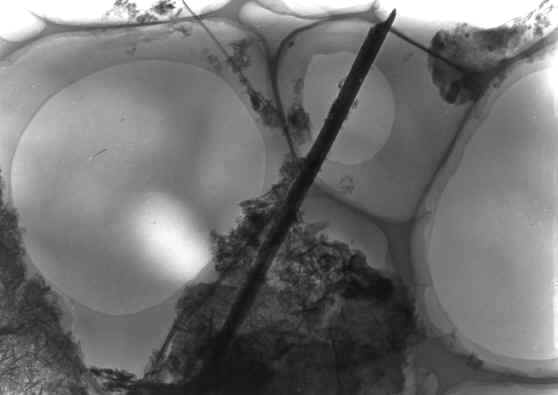

L'obiettivo della AFeVA Sardegna non è solo quello di denunciare e lottare contro i gravi danni alla salute delle persone che l'amianto provoca ma anche partecipare attivamente alla discussione propositiva con il fine esclusivo di porre fine alla drammatica, ancora irrisolta, emergenza sanitaria e sociale causata dall'amianto in Sardegna, in Italia, in Europa, nel Mondo.